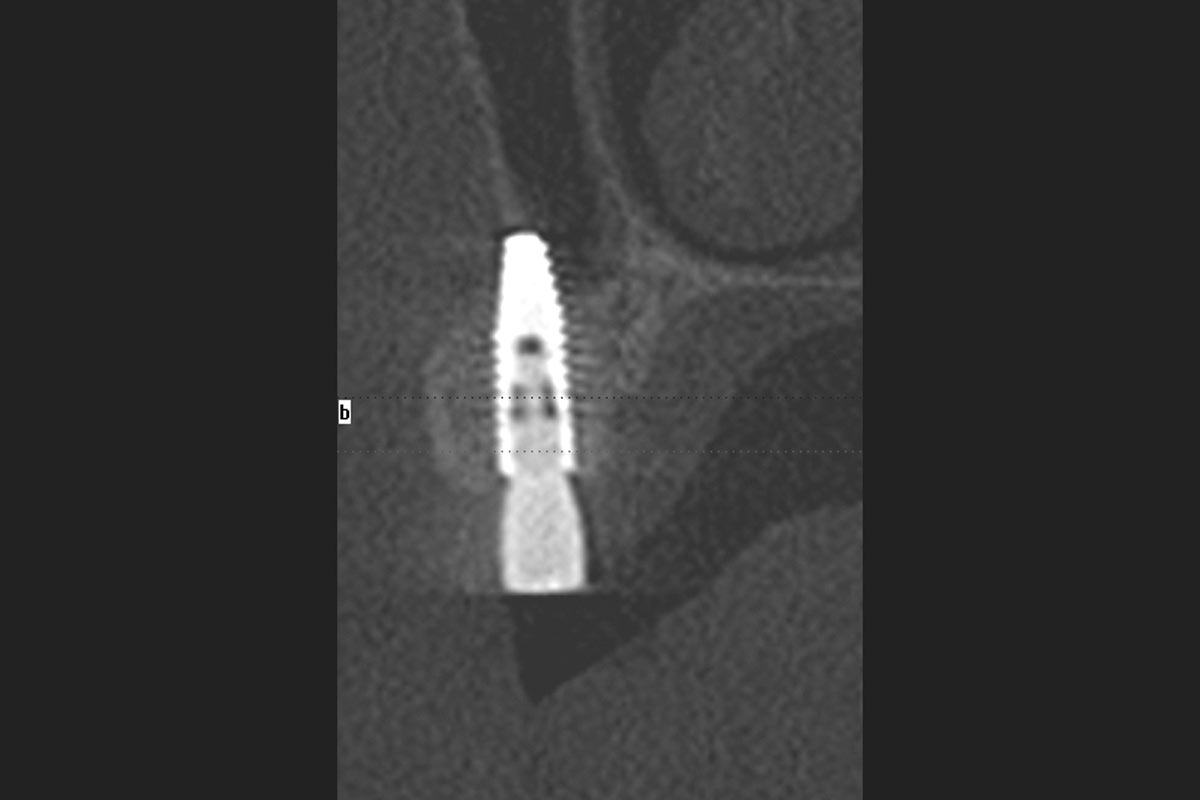

Bone defect in area 11-21 due to two lost implants (periimplantitis) after 15 years of function